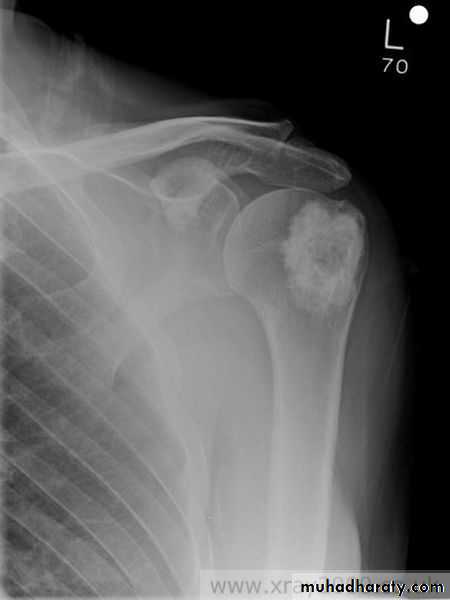

Sclerotic metastases appear as ill-defined areas of increased density of varying size with ill-defined margins .

1-in men they are most commonly due to metastases from carcinoma of the prostate .

2-in women from carcinoma of breast , metastases with bone expansion occurs in primary tumour of the kidney & thyroid .